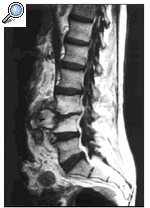

- Resonancia magnética de la columna

- Tomografía computarizada de la columna